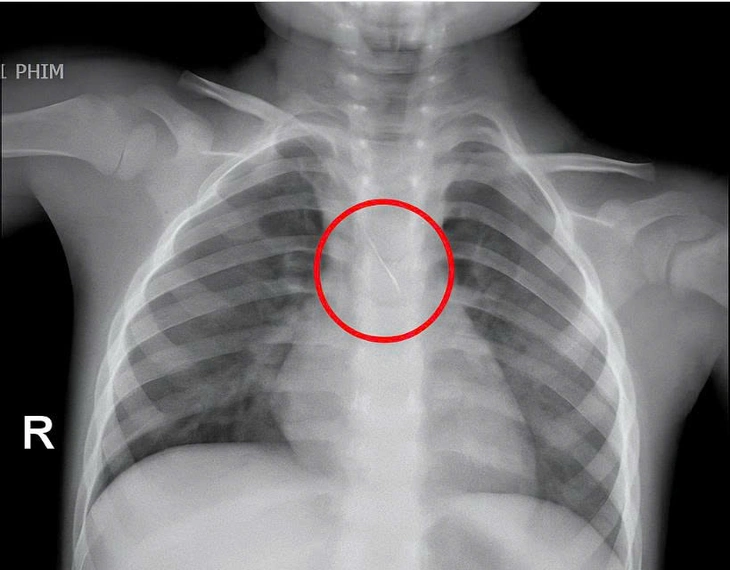

Dị vật trong đường thở cháu bé.

Trước đó bệnh viện tiếp nhận bé N.Q.T.Đ. (3 tuổi), trú tại xã Cửa Việt, Quảng Trị, trong tình trạng ho nhiều, ho sặc. Kết quả chụp phim cho thấy một dị vật kim loại dài khoảng 22mm nằm ở góc carina (vị trí chia đôi khí quản) đe dọa gây tắc nghẽn đường thở của trẻ.

Ngay lập tức, các bác sĩ hội chẩn liên khoa và quyết định nội soi phế quản cấp cứu. Dị vật được phát hiện có một đầu nhọn cắm vào 1/3 dưới khí quản, đầu còn lại nằm trong phế quản gốc trái, được xác định rất nguy hiểm.